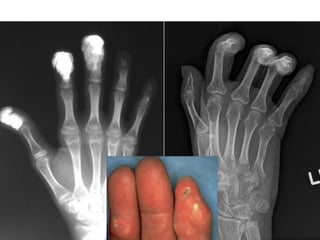

Skeletal manifestations of

scleroderma

Location:

• The hands are the most common location.

Bone changes:

• Acro-osteolysis (resorption of terminal phalanges).

• Joint space narrowing.

• Erosions.

Soft tissue changes:

• Subcutaneous & peri-articular calcification.

• Atrophy specially at the tips of finger.

• Flexion deformities.

Acro-osteolysis

terminal phalanx resorption